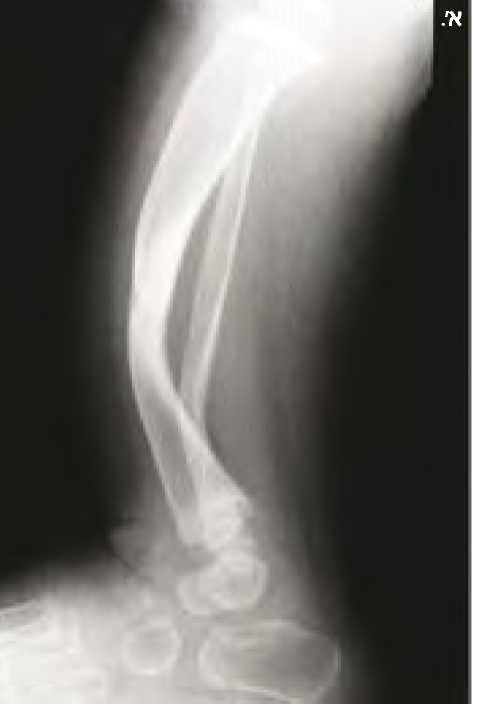

בנוירופיברומטוזיס מסוג 1 קיימות פגיעות שלדיות רבות. המעורבות הגרמית היא לרוב קלה ולעתים אף מהווה קריטריון אבחנתי למחלה, כמו למשל דיספלזיה (Dysplasia) של עצם היתד (Sphenoid) (תמונה 6) או אי חיבור (Pseudoarthrosis) של עצם השוקה (Tibia) (תמונה 7). בעיות שכיחות יותר הן קומה נמוכה (כ-30%) ועקמת (כ-10%). לעתים נצפים מקרים קשים של עקמת ועקשת (Kyphoscoliosis) המחמירים במהלך החיים ומסכנים את תפקוד הריאות והלב ודורשים התערבות ניתוחית (תמונה 8). כ-50% מהמבוגרים עם נוירופיברומטוזיס מסוג 1 מפתחים ירידה בצפיפות העצם (Osteoporosis) וזקוקים לאבחון וטיפול תרופתי בהתאם.

- נגעים גרמיים אופייניים כגון דיספלזיה של עצמות היתד בגולגולת או אי חיבור של עצם השוקה